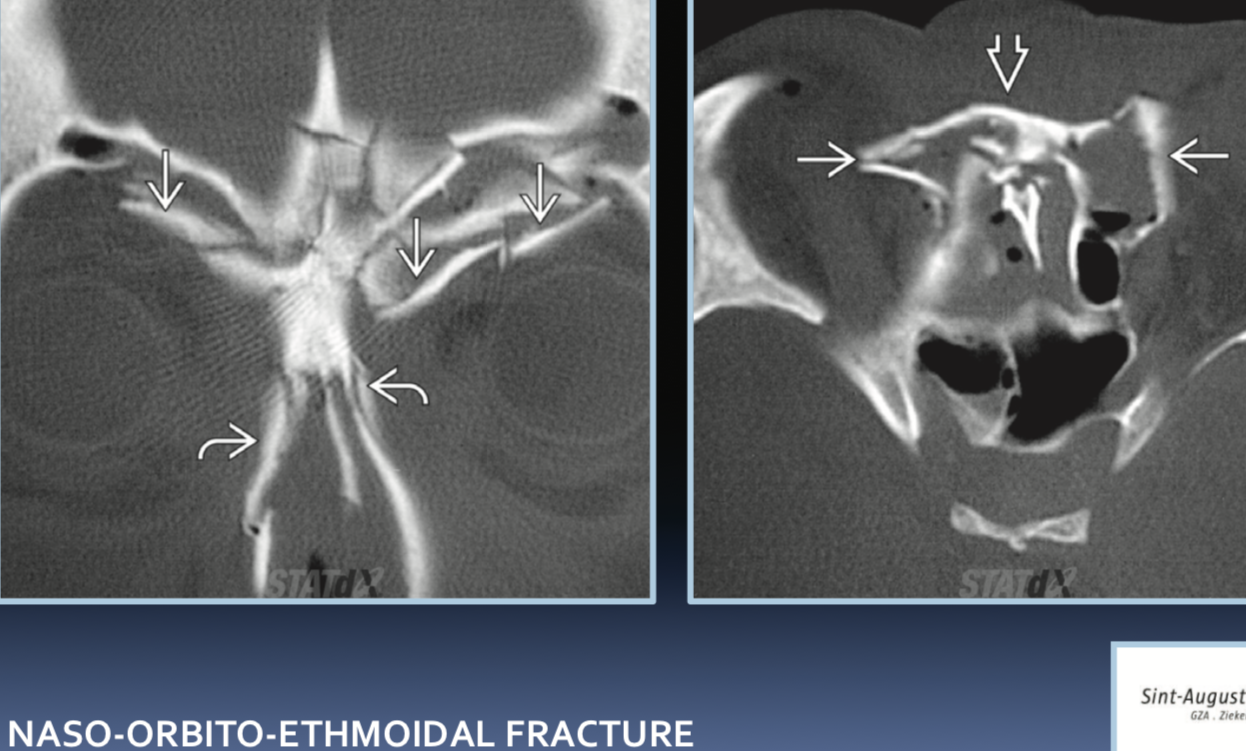

Naso-orbito-ethmoidal fracture. What to report on CT?

Naso-orbital-etmoidal fractures complications?